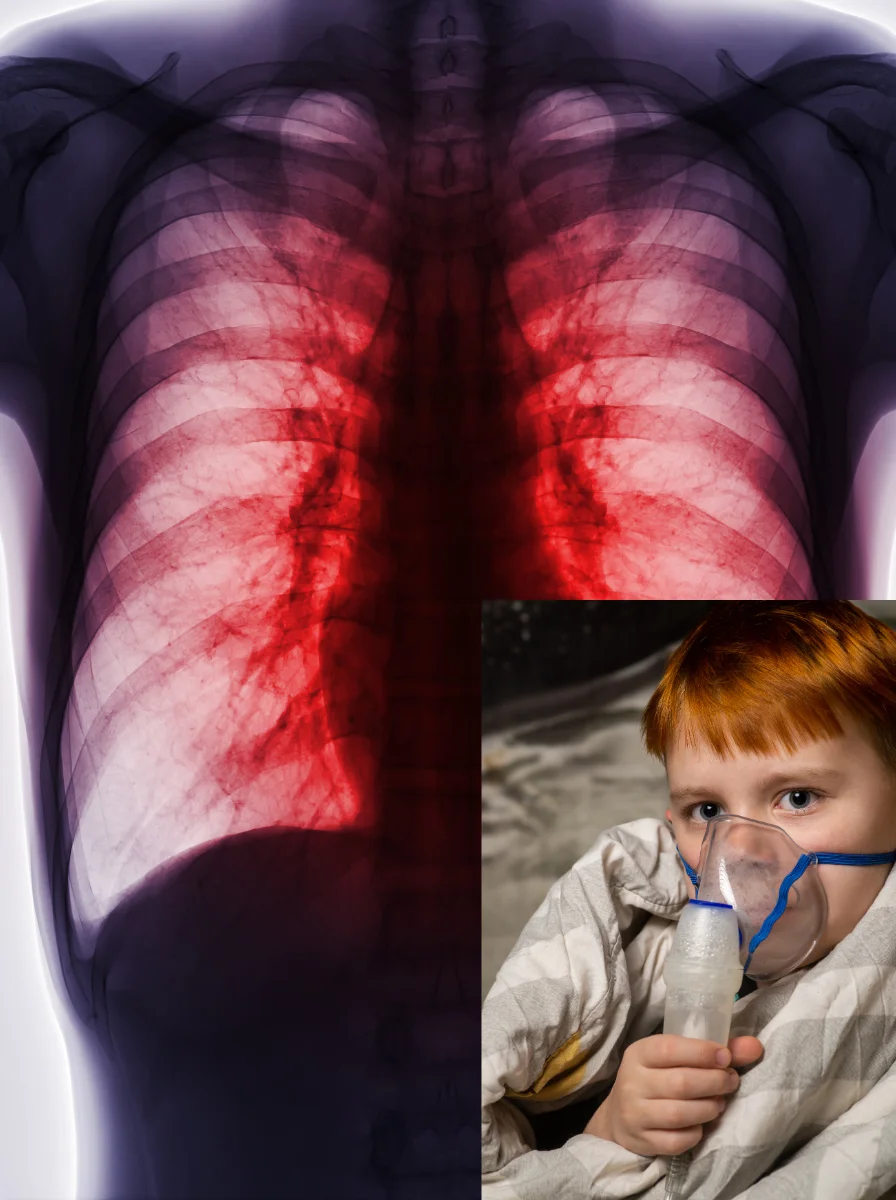

Critical Care Hospital offers the Best Respiratory Treatment in Ahmedabad for patients suffering from acute and chronic lung conditions. Our expert team provides ICU-based respiratory care, advanced ventilator management, and evidence-based therapies for critically ill patients.

Respiratory diseases affect the lungs and airways, leading to difficulty in breathing, reduced oxygen levels, and systemic complications if untreated. These conditions may be acute, chronic, or life-threatening, requiring specialized critical care support.

Understanding Asthma

A chronic inflammatory airway disease causing recurrent episodes of wheezing and breathlessness.

Bronchodilator and nebulization therapy

Medications delivered by inhalation to open airways reduce bronchospasm and improve airflow.